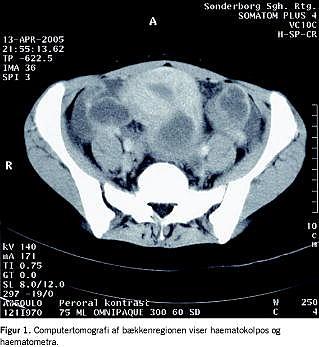

En 14-årig, tidligere rask pige henvistes akut af en vagtlæge til en kirurgisk afdeling på mistanke om nyrelæsion. Pigen var fire dage forinden faldet på sengekanten, hvor hun slog halebenet. Den følgende dag fik hun smerter i epigastriet og højre flanke. Smerterne tiltog betydeligt over de næste dage på trods af analgetisk behandling, hvorfor pigen opsøgte vagtlægen. Denne konstaterede mikrohæmaturi og fandt patienten smertepåvirket og klamtsvedende. Ved indlæggelsen klagede pigen foruden smerter over kvalme. Der var normal afføring. Ingen dysuri eller opkastning. Pigen havde ikke haft menarche. Objektivt fandtes hun febril, 38,8° C. Hun var diffust øm i abdomen og over begge nyreloger, og man bemærkede en palpapel udfyldning over symfysen. Der var veludviklede mammae og normal kvindelig pubesbehåring. C-reaktivt protein var 202 mg/l, leukocytter 9,3 × 10 9 /l, serumkreatinin 71 mmol/l. På mistanke om organlæsion som årsag til symptombilledet blev der foretaget akut computertomografi (CT) af abdomen. Denne udførtes med peroral og intravenøs kontrast med leveren i portokaval fase og viste massiv haematometra og haematokolpos, venstresidig hydronefrose og hydroureter samt en mindre væskeansamling intraperitonealt (Figur 1 ). På mistanke om HI overførtes pigen herefter til en gynækologisk afdeling, hvor man ved inspektion bekræftede diagnosen. På grund af den perorale kontrast, valgte man ikke at operere akut og foretog i stedet en lille incision i hymen, hvorved der udtømtes 500 ml gammelt blod. Man påbegyndte antibiotisk behandling, og pigen blev opereret dagen efter i fuld anæstesi, hvor introitus dilateredes til tre fingre. Podning fra vagina samt dyrkning af blod og urin var uden vækst. Pigen blev udskrevet afebril og velbefindende to døgn efter. Ved ambulant kontrol tre måneder senere var hun velbefindende og havde fået regelmæssige menstruationer. Ved en abdominal ultralydskanning (UL) fandtes normale forhold i genitalia interna.